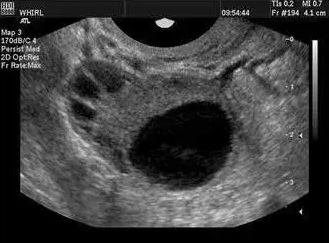

卵泡的正常生長受卵巢自身功能和下丘腦-垂體-卵巢軸以及中樞神經系統、內分泌系統的復雜影響。一般情況下,精子的壽命為2--3天,而排卵后卵子的壽命較短,15小時即會逐漸衰老;因此,排卵前兩天至排卵后10小時是受孕的關鍵時間。當卵泡直徑>10mm時,稱優勢卵泡;卵泡直徑達>18mm時,稱成熟卵泡。

一般認為成熟卵泡直徑在18-25mm,妊娠機率較大,卵泡直徑<18mm則不易妊娠。所以說卵泡發育不良,不能正常排卵或者排出的卵子質量不好,都會影響正常的受孕生育。